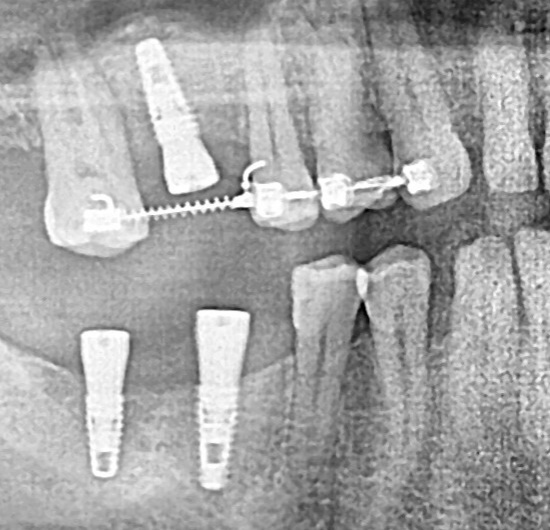

Ранее удаленный зуб 36 - незначительная атрофия по костным тканям и довольно выраженная атрофия по мягким тканям.

Имплант Straumann BLT 4.1*8mm SLActive - установлен в субкрестальное положение, произведено профилирование кортикальной кости системой Straumann Bone Profiler с целью создания более выгодного профиля прорезывания и исключения костной резорбции в области шейки импланта.

Чтобы компенсировать недостаточный объем мягких тканей проведена - мягкотканая пластика деэпителизированным соединительнотканным трансплантантом с неба.

Установлен заживляющий абатмент диаметром 6.5 мм.

Обратите внимание на объем и качество мягких тканей в области будущей финальной реставрации!